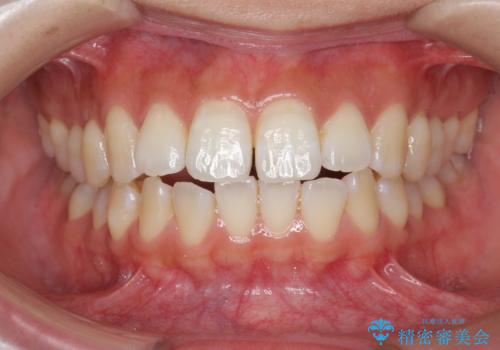

- 前歯の噛み合わせの開きの改善を求めて来院されました。

奥歯はほとんど動かさず(奥歯の噛み合わせはほとんど変えず)前歯のIPR矯正でガタつき前突感(出っ歯感)の改善を計画します。

ほとんど前歯のみの矯正治療であることからトータル14枚のマウスピースで並べるインビザラインライトによる治療を行います。